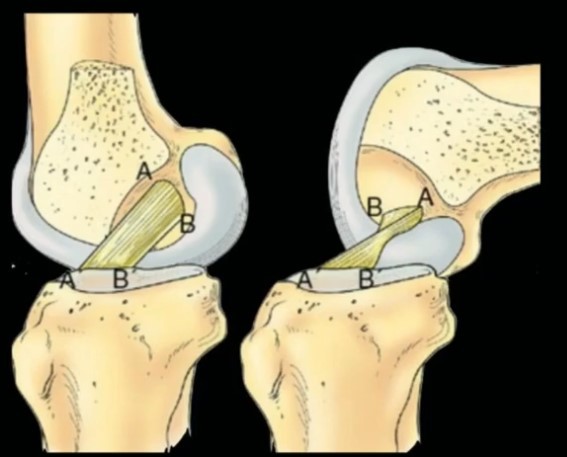

Quais bandas agem na flexo-extensão

Banda AM Tensa em flexão

Banda PL Tensa em extensão